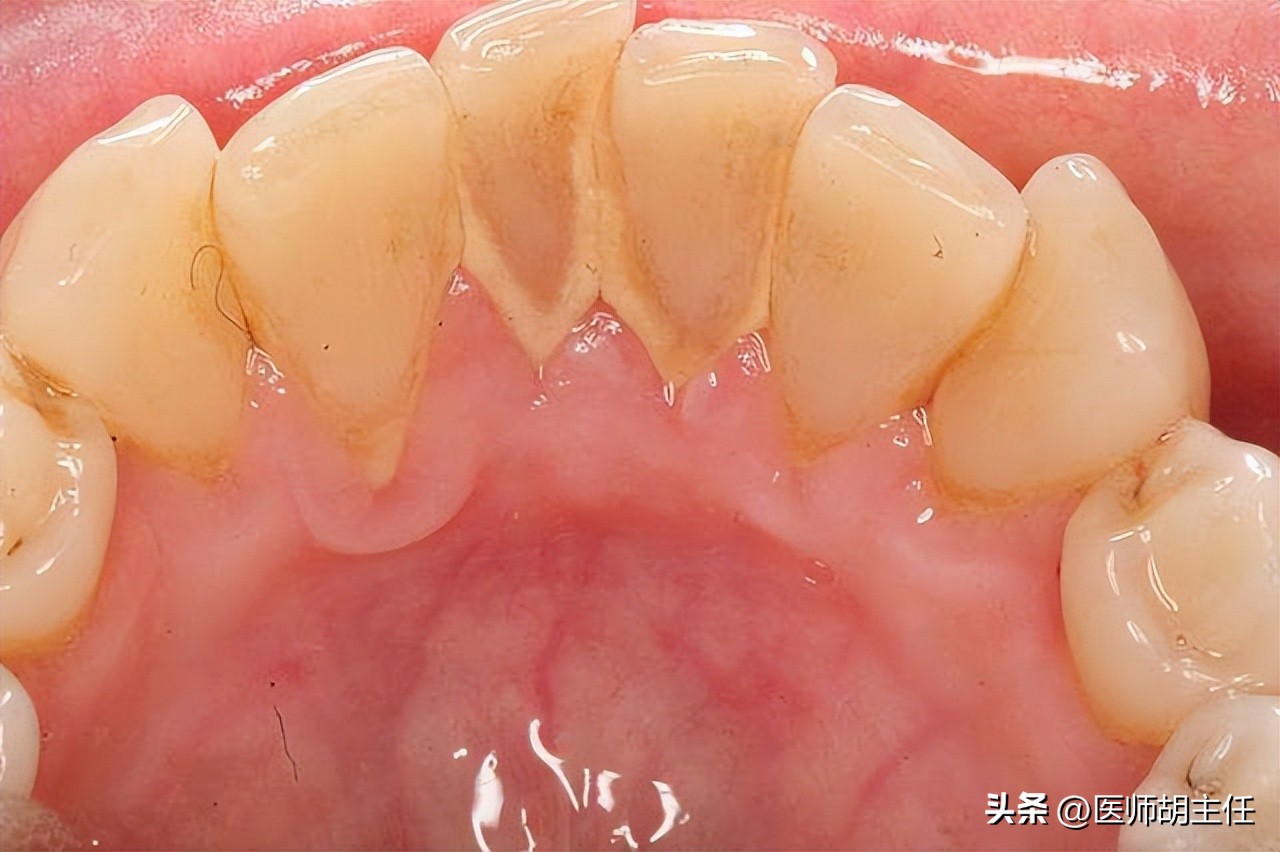

现在赵先生已经开始担忧起来,生怕是什么其他的疾病,于是赵先生前往我院口腔科进行诊治,待赵先生一张开嘴巴, 医生戴着口罩也闻到了一阵阵臭味传出来, 仔细一番检查,发现赵先生舌面、唇面和两侧结石都有很厚的牙石,诊断为 牙周炎、重度牙结石和牙龈萎缩 。

轻度就是整个口腔只有一点点牙石,需要去寻找;中度就是口腔有牙结石,但没有超过附近牙齿的三分之一;重度就是在中度的基础上,超过了附近牙齿的三分之一; 像赵先生这种,已经是达到重度了。